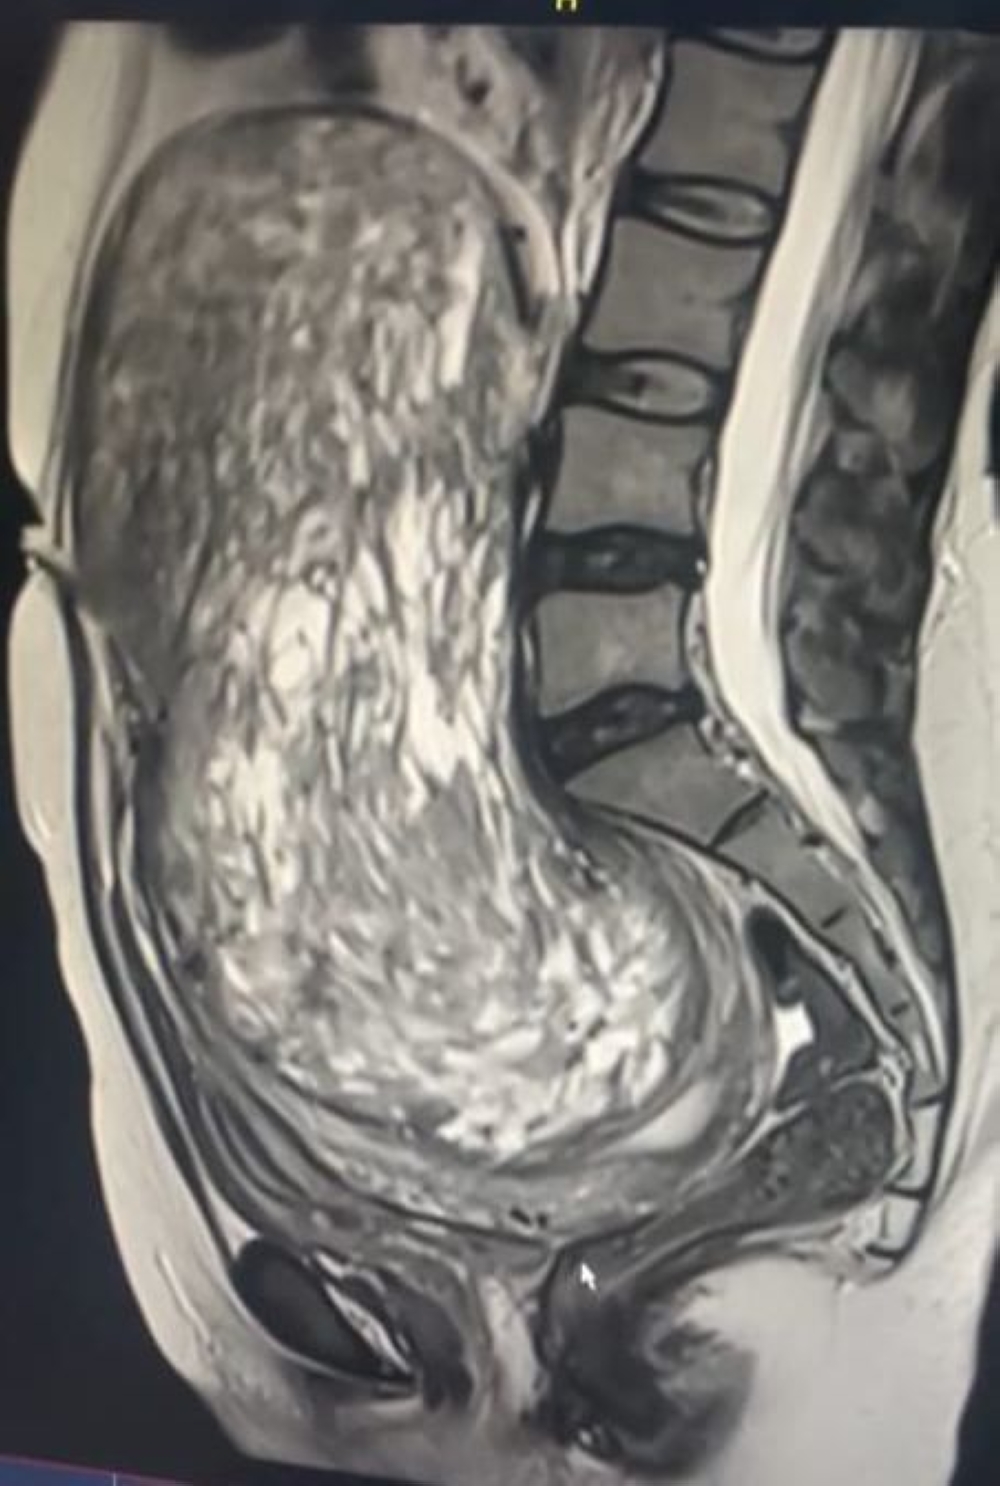

نجح فريق طبي في مدينة الملك عبدالله الطبية بمكة المكرمة، في إجراء عملية جراحية دقيقة لاستئصال ورم بحجم جنين من سيدة سعودية تبلغ من العمر ثلاثين عامًا. كانت المريضة تعاني من آثار سلبية للورم الذي ضغط على الشريان الأورطي والوريد الأجوف السفلي، مما أدى إلى انسداد جزئي في الجهاز الهضمي وإمساك مزمن، بجانب الضغط على المثانة البولية والأعصاب، مما تسبب لها في آلام وتنميل بالأطراف السفلية.

تم إجراء العملية بعد إجراء فحوصات مخبرية وتصوير دقيق، بالإضافة إلى تقييم شامل من قسم التخدير لضمان الأمان الطبي. تم استئصال الورم بالكامل عبر فتح البطن دون التأثير على الرحم والمبيضين. استغرقت العملية حوالي ثلاث ساعات وحققت نتائج إيجابية، حيث تماثلت المريضة للشفاء بشكل كامل.